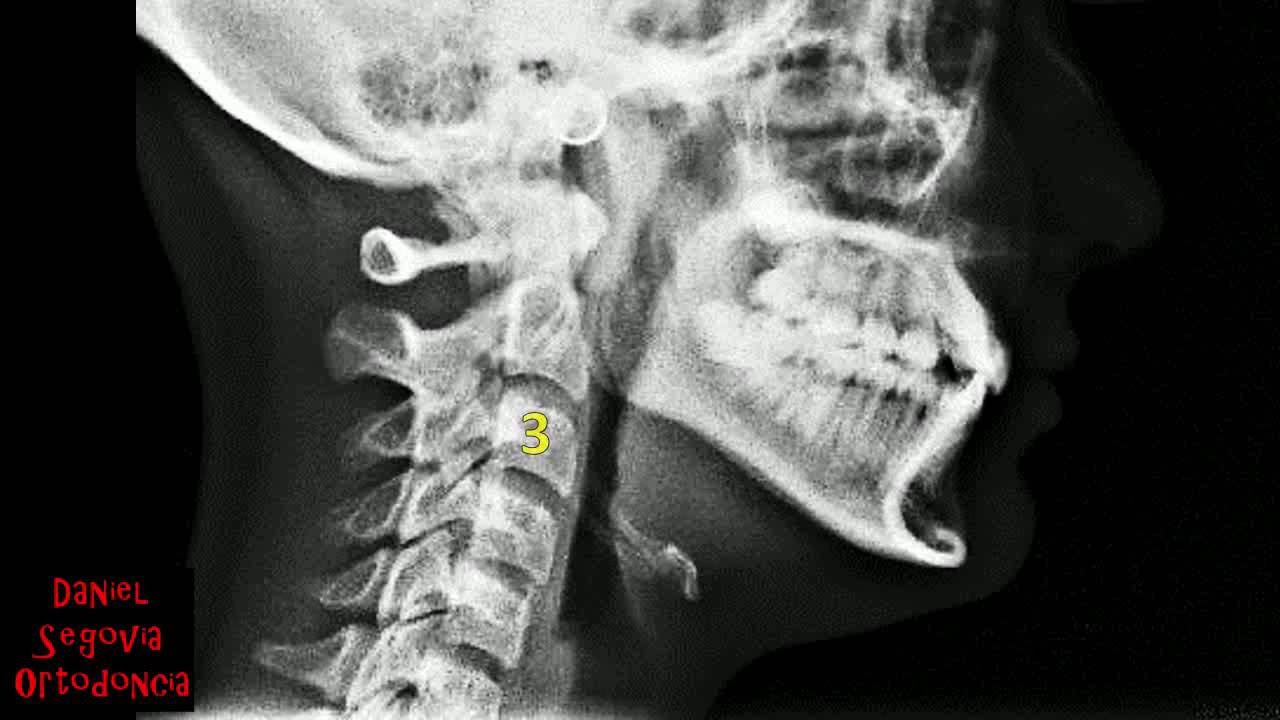

Evaluación cefalométrica rápida del hioides en ortodoncia

Описание: Diagnosticar la posición del hueso hioides es muy importante ya que influye en la postura lingual en reposo y durante el sueño. Existen diversos cefalogramas al respecto. En el video se describe un método rápido (aunque impreciso) para valorar visualmente la posición.